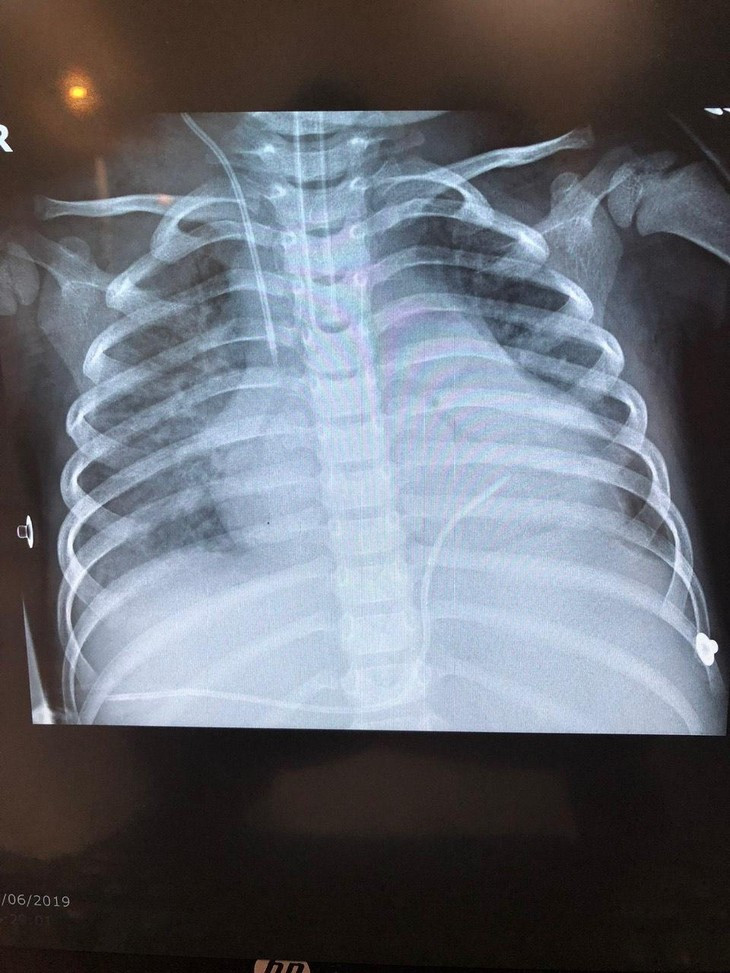

Ảnh xquang em bé 3 tuổi bị tràn dịch đa màng: màng bụng, màng tim, màng phổi do sán lá gan lớn.